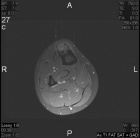

21 year old male with increasing leg pain and enlarging mass for three years